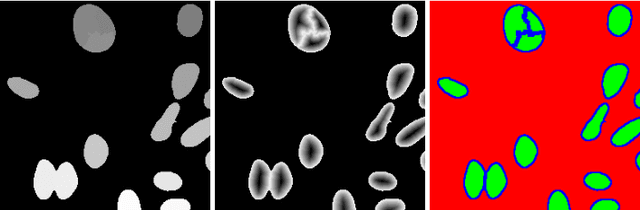

Abstract:Cell instance segmentation in fluorescence microscopy images is becoming essential for cancer dynamics and prognosis. Data extracted from cancer dynamics allows to understand and accurately model different metabolic processes such as proliferation. This enables customized and more precise cancer treatments. However, accurate cell instance segmentation, necessary for further cell tracking and behavior analysis, is still challenging in scenarios with high cell concentration and overlapping edges. Within this framework, we propose a novel cell instance segmentation approach based on the well-known U-Net architecture. To enforce the learning of morphological information per pixel, a deep distance transformer (DDT) acts as a back-bone model. The DDT output is subsequently used to train a top-model. The following top-models are considered: a three-class (\emph{e.g.,} foreground, background and cell border) U-net, and a watershed transform. The obtained results suggest a performance boost over traditional U-Net architectures. This opens an interesting research line around the idea of injecting morphological information into a fully convolutional model.